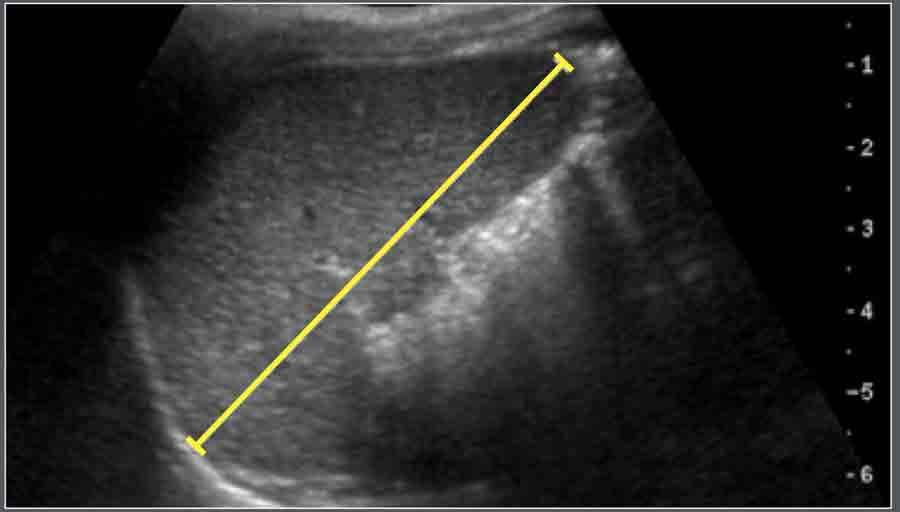

Gan

Kích thước đầu-đuôi của gan được đo dọc theo đường trung đòn bằng siêu âm.

Trẻ em

Vật liệu và Phương pháp

Nghiên cứu siêu âm trên 307 trẻ em khỏe mạnh.